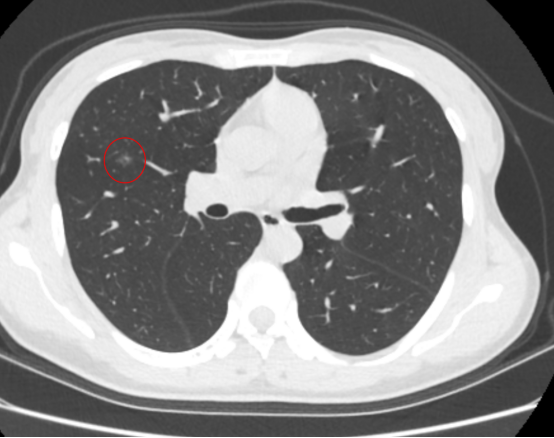

图中红圈内为该患者肺磨玻璃病灶

半个月前,她复查胸部CT发现肺内结节较前增大,进一步做了PET-CT检查,考虑原位或微浸润癌可能大。